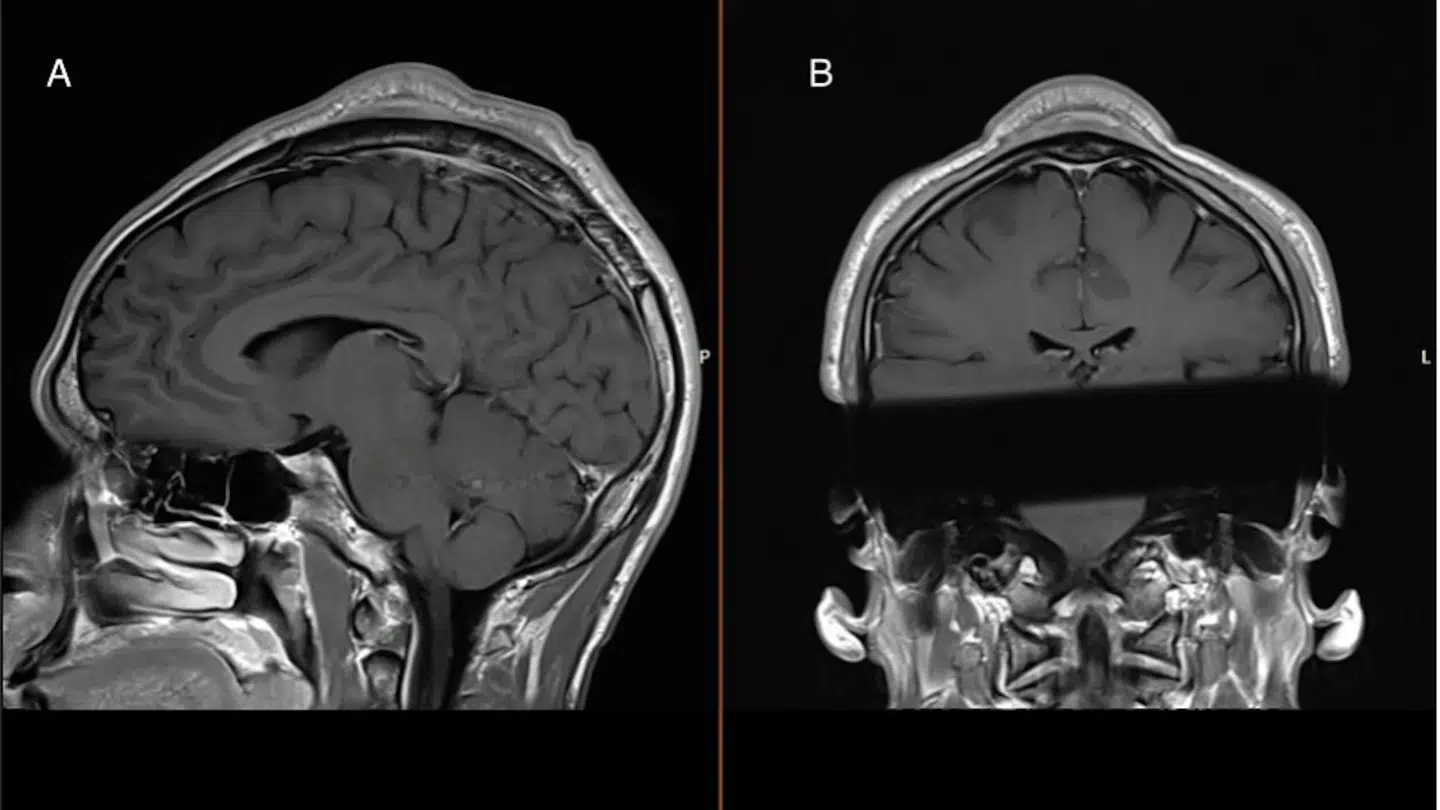

Sagen er, at lægerne blev opsøgt af den danske breakdancer, der var træt af en temmelig markant bule i sit hoved. Da lægerne scannede bulen, viste det sig at være en godartet svulst.

Bulen kaldes meget præcist for et ‘headspin hole’ eller en ‘breakdance bulge’. Første stadie i tilstanden er 'skaldethed, som følge af slitage', forklarer Christian Baastrup Søndergaard.

»Der sker det, når man laver headspins, at håret udtyndes. Det kan give en bar plet eller skaldethed. Men med tiden udvikler man en egentlig bule af arvæv under huden,« siger han.

Han forsikrer, at tilstanden ikke er farlig, men kan være en gene for patienterne. I det konkrete tilfælde lå svulsten uden på kraniet og har derfor ikke påvirket hjernefunktionen hos den mandlige hip hop danser.